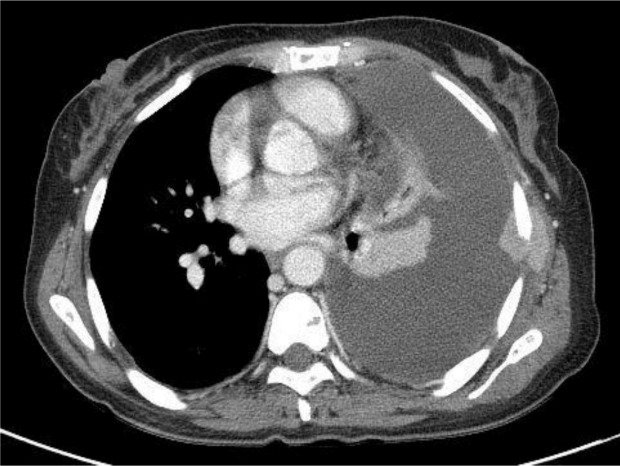

Figure 1.

Chest computed tomography scan. Left pleural effusion of large volume was detected, and extraosseous plasmacytomas in the left chest wall was increased in size.

과거력: 2013년 4월 4일 혈청면역전기영동(immunofixation electrophoresis) 검사에서 음성이었고, 혈청단백전기영동(protein electrophoresis) 검사에서 M-peak 소견은 보이지 않았으며, serum free light chain Kappa/Lambda ratio (sFLC)에서 0.035, 골수 조직검사에서 형질세포(plasma cells)가 2.2% 포함되어 free lambda 아형의 다발성 골수종이 진단되었다. 2013년 4월부터 8월까지 vincristine, adriamycin, dexamethasone (VAD) 관해유도요법 4주기 시행 후 2013년 9월 말초혈액조혈모세포이식을 시행하였고, 2015년 1월 재발하여 1월부터 2월까지 velcade, dexamethasone (VD) 복합화학요법 2주기를 시행하였으며 이후 불응 소견으로 2015년 3월부터 5월까지 cyclophosphamide, lenalidomide, dexamethaxone (CRD) 복합화학요법 3주기를 시행하였다. 2015년 6월 2일 좌측 흉수로 인한 호흡곤란을 호소하여 입원하였고, 흉부 전산화단층촬영에서 다량의 좌측 흉수가 보이며 좌측 흉벽에서 체외뼈 형질세포종(extraosseous plasmacytomas)의 크기가 증가하였다(Fig. 1). 흉수 천자 검사에서 fluid pH 7.22, fluid cell count white blood cell (WBC) 130개/μL, red blood cell (RBC) 90,000개/μL (poly 2%, lympho 10%, macro 10%, others 78%), ADA 43.6 IU/L, lactate dehydrogenase (LDH) 676 U/L, total protein 3.5 g/dL, albumin 2.5 g/dL, glucose 70 mg/dL이며 흉수의 세포병리 검사에서 일부의 형질세포종이 의심되는 비정형세포들(atypical cells)이 관찰되었고 sFLC 수치는 2015년 4월 27일 0.316 (kappa/lambda = 10.24 mg/L/32.38 mg/L)에서 0.077 (7.63 mg/L/98.69 mg/L)로 감소하여 골수종 흉수로 진단하였다. 2015년 6월 5일부터 7월 29일까지 DCEP 복합화학요법으로 변경하여 2주기를 시행하였고 sFLC 수치는 0.557 (4.91 mg/L/8.81 mg/L)로 상승하며 환자는 호흡곤란 증상이 호전되어 퇴원하였다.